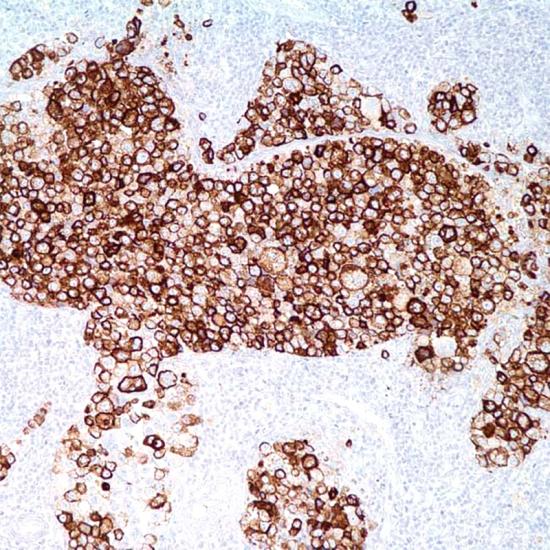

Mesothelioma

MC抗體試劑(免疫組織化學(xué)) 閩廈械備20180072號(hào)

• 陽(yáng)性部位:

細(xì)胞漿/細(xì)胞膜

• 陽(yáng)性對(duì)照:

間皮瘤

Mesothelioma在正常、增生的間皮和間皮瘤均有表達(dá),在上皮型、混合型間皮瘤的上皮樣成分陽(yáng)性,梭形細(xì)胞間皮瘤呈陰性反應(yīng)??寺√?hào)HBME-1標(biāo)記甲狀腺乳頭狀癌和濾泡狀癌,但在正常的甲狀腺不表達(dá),因此可用來(lái)鑒別甲狀腺的良惡性病變。MC對(duì)間皮瘤(陽(yáng)性率較高)和腺癌(陽(yáng)性率較低)的鑒別也有一定意義。